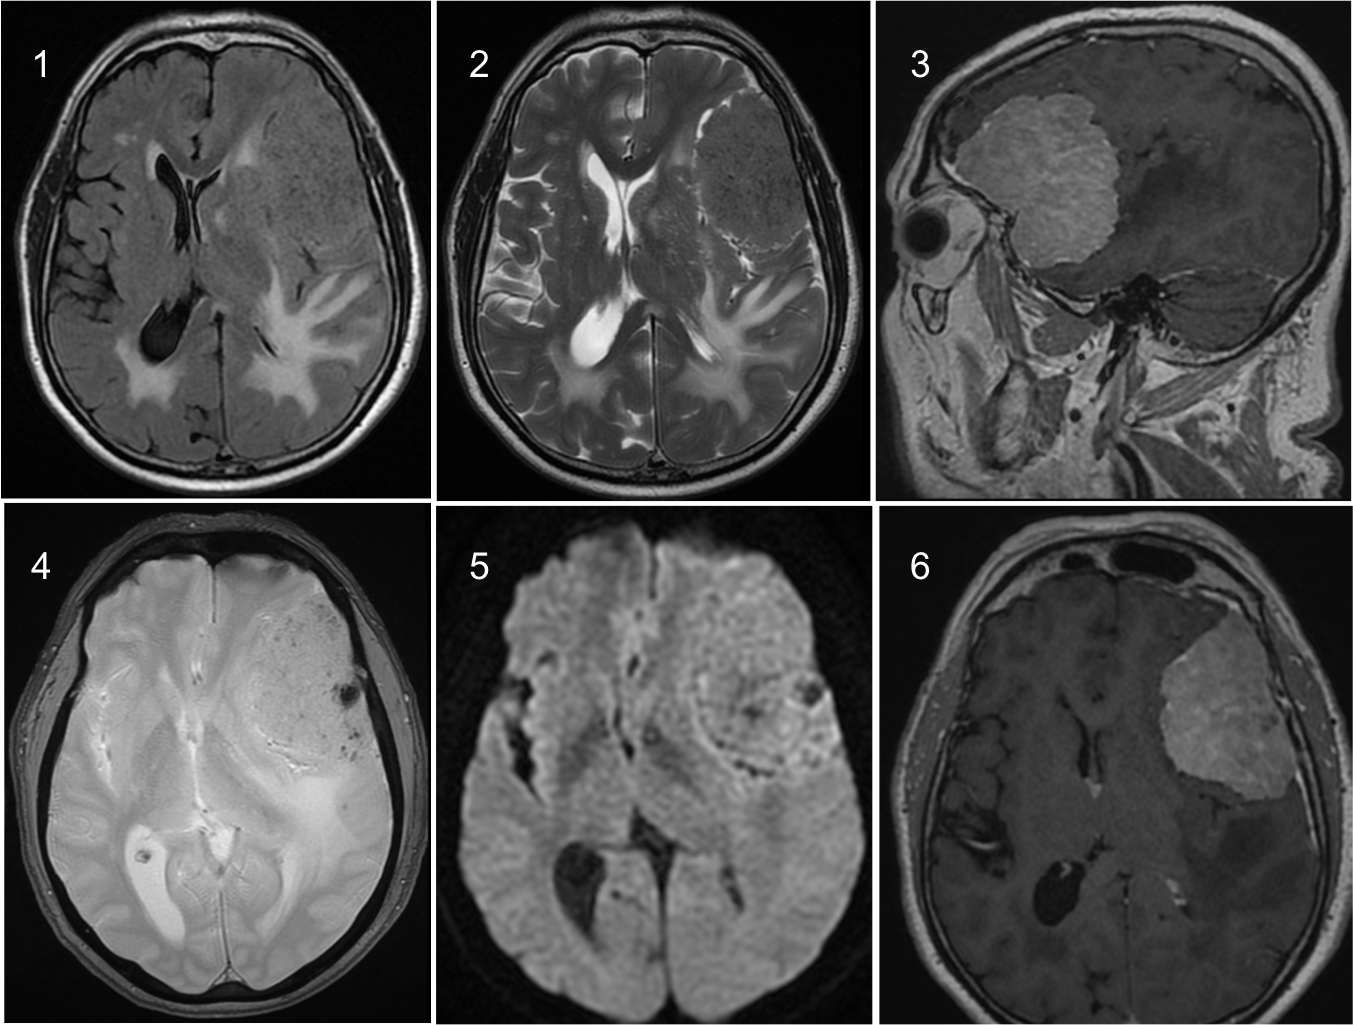

Cirugía Tumor Cerebral

Cirugía de tumor cerebral con enfoque de máxima precisión y técnicas mínimamente invasivas, priorizando la seguridad neurológica y la recuperación funcional.